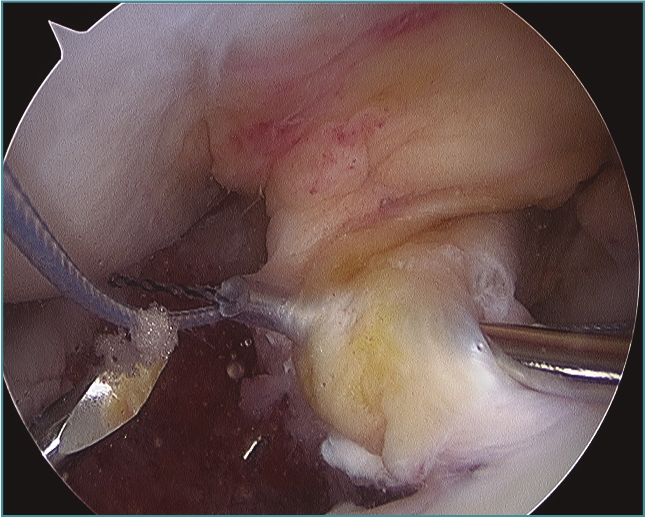

Fractura-avulsión de la eminencia tibial en varón de 14 años. Imagen obtenida durante la reparación artroscópica mediante sutura en 4 puntos, en la que se observa el pase indirecto de la sutura a través del ligamento cruzado anterior (LCA).